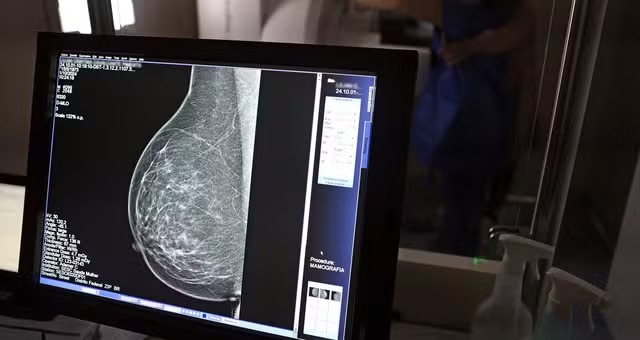

Segundo os pesquisadores, a tecnologia consegue identificar o acúmulo de cálcio nas artérias da mama por meio das imagens de raio-x usadas normalmente no rastreamento do câncer de mama. Esse tipo de calcificação, apesar de não ter relação com tumores, já vinha sendo associado em estudos anteriores a um maior risco de doenças cardíacas.

A análise foi feita com o apoio de inteligência artificial em exames de 123 mil mulheres que participaram de programas de rastreamento e não tinham diagnóstico prévio de doença cardiovascular. O sistema avaliou a quantidade de depósitos de cálcio nas artérias do tecido mamário e classificou os casos como calcificação leve, moderada, grande ou ausente.